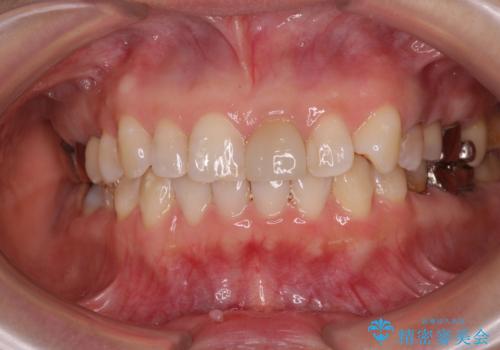

当院では治療前の歯列が整っていない限り、下顎前歯の舌側をワイヤーで固定するようにしています。下顎のみの部分矯正としたことで、マウスピース保定の負担を軽減することができました。

上顎は、失活して歯の色が変色しているため、将来的に補綴治療で自然な口元に仕上げていきたいとのことでした。